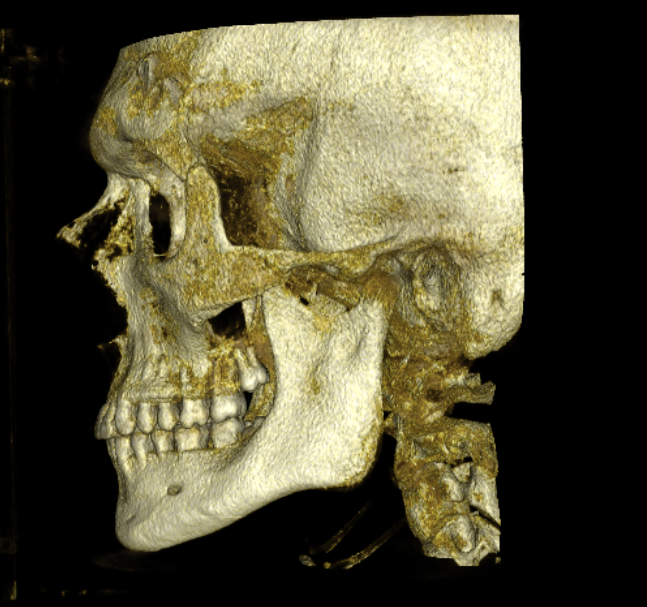

I ran every ratio I could measure. Front and side. Categorized them from ideal all the way down to severely insufficient. I'm not going to list every number because even for this forum that would be weapons grade autism, but here's what matters.

A lot of things work. More than I expected honestly. My vertical proportions are basically textbook. All three thirds sitting exactly where they should be. Midface ratio, ideal. Interpupillary to mouth width, ideal. Bitemporal width, ideal. Eye aspect ratio, ideal. From the side the story is similar. Facial convexity, correct. Nasomental angle, ideal. Nasolabial angle, solid. Ramus to mandible ratio, good.

Maxillomandibular recession.

Every. Single. Ratio. That scored badly traces back to this. Every single one. The recession relative to the Frankfort plane is genuinely terrible. The Z angle is dragging. The submental cervical angle is one of the worst measurements on my entire face, and it's not because I'm fat, it's because the chin and mandible literally don't project far enough to hold the soft tissue up. From the front the jaw angle is way too obtuse when it should be approaching 90 degrees. The deviation between my alar angle and jaw frontal angle is enormous.

And the midface? Yeah, the cheekbones are flat and they sit way too low. One of my absolute worst scores. But here's what most people would miss: the flat midface isn't purely a zygomatic issue. The entire maxillary complex is sitting too far back. The face doesn't project forward as a unit. The zygos being low is real, but the recession underneath is what makes the whole thing look as bad as it does.

CBCT RENDERS

All attached. Frontal bone, left lateral, right lateral, soft tissue overlays, volume renders at different thresholds. The full skull, nothing hidden, nothing frauded with angles. You can see every problem I just described for yourself.

CBCT RENDERS

All attached. Frontal bone, left lateral, right lateral, soft tissue overlays, volume renders at different thresholds. The full skull, nothing hidden, nothing frauded with angles. You can see every problem I just described for yourself.